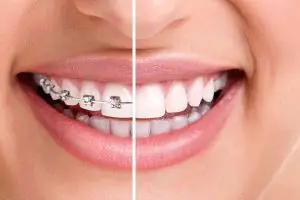

Have you chosen the right way to straighten tiger teeth?

Tiger teeth are canine teeth, which are the two single fangs of the upper jaw, which protrude outward at the age of twelve or thirteen,